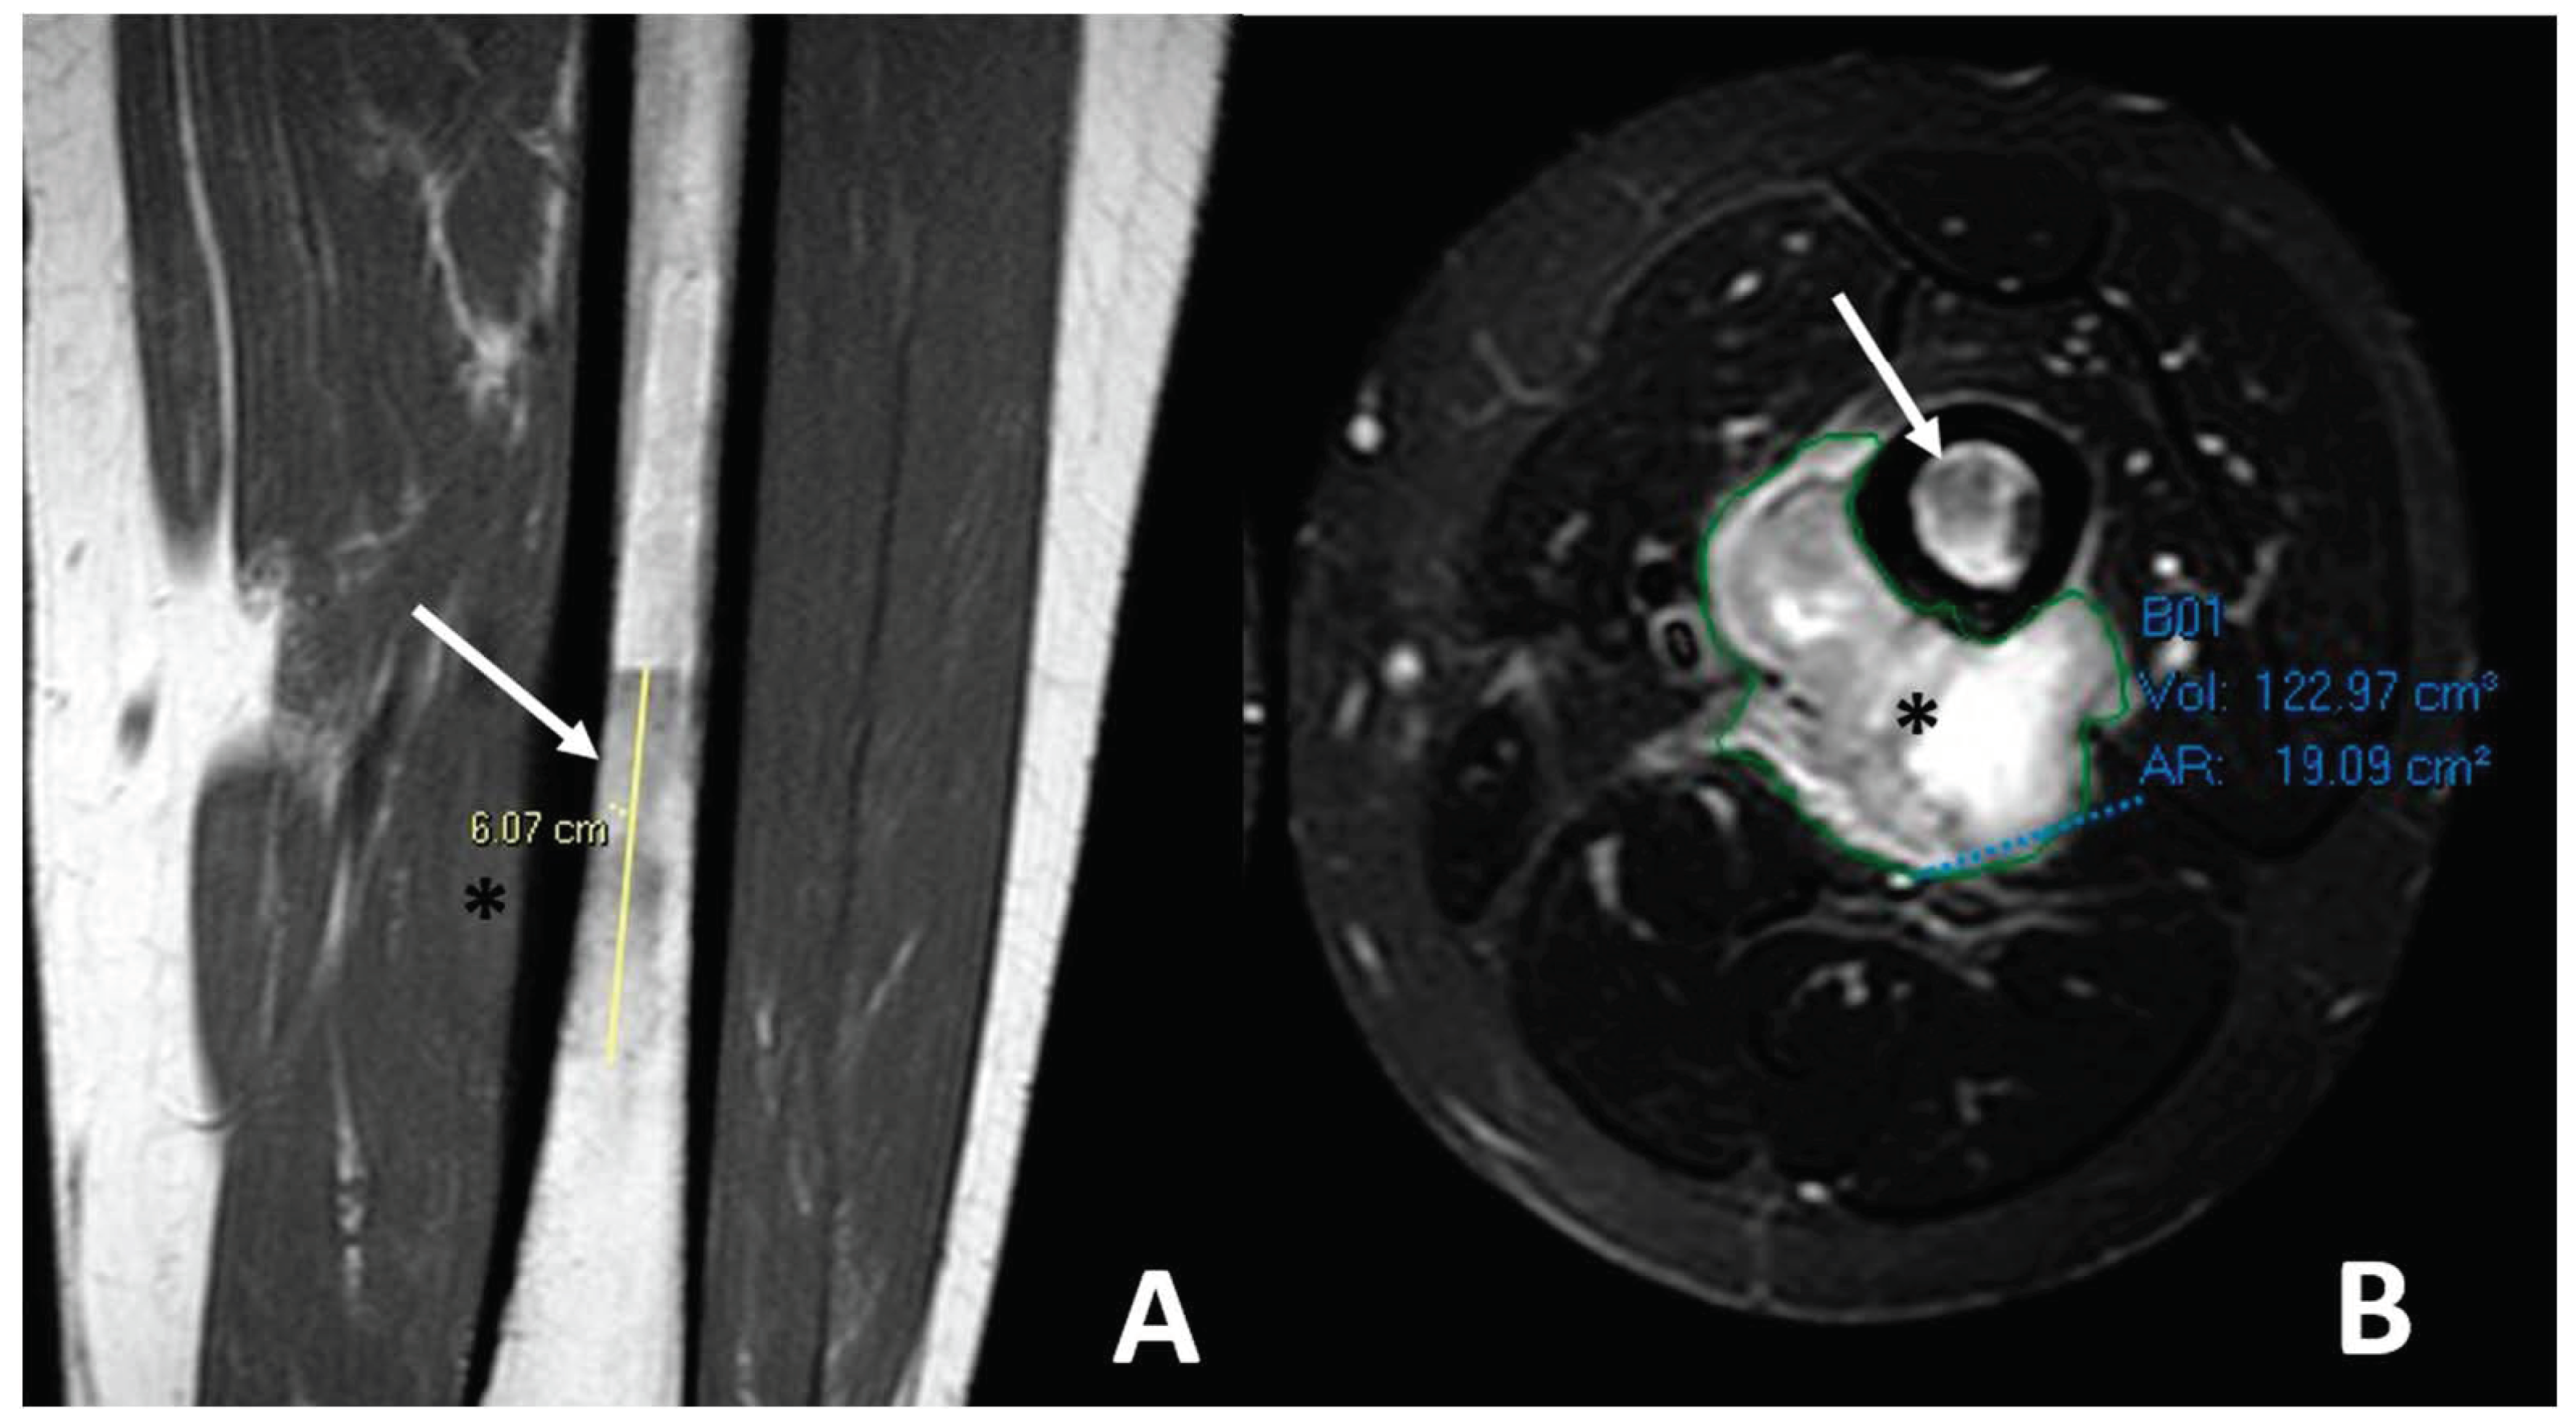

2.4. Radiological Findings on MRI

| Telangiectatic | Purely osteolytic | None or thin regular | Multicystic pattern with fluid–fluid levels and solid components on MRI |